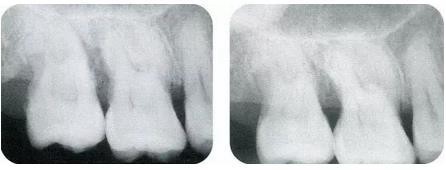

▼圖13-7,8 術(shù)前與術(shù)后8個月的x片。牙槽骨明顯改善。

▼圖14-9~13 術(shù)后每2個月拍一次x片,檢查牙槽骨的變化??纱_認(rèn)有顯著的骨增加。